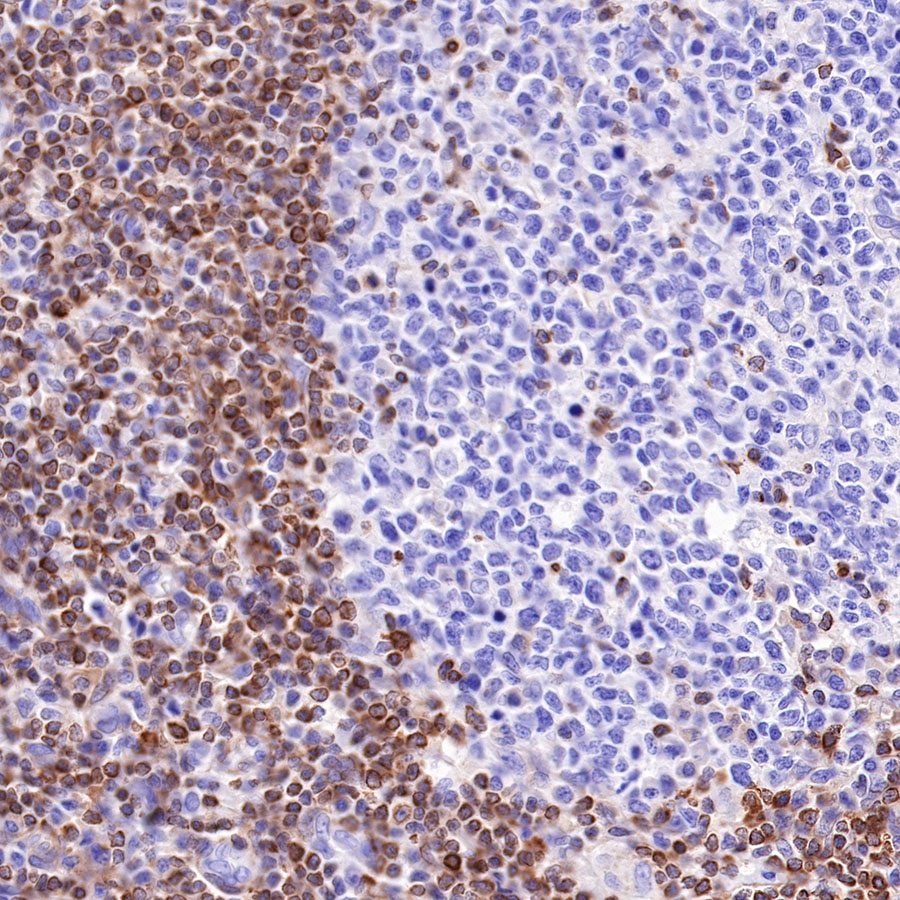

Picture

Immunohistochemistry